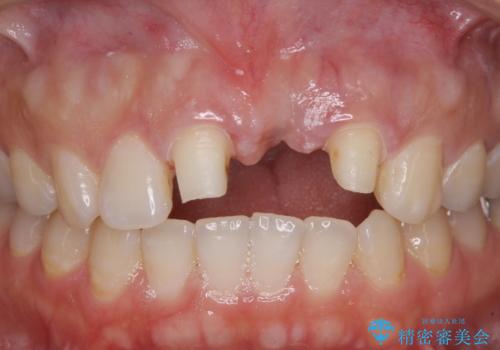

- 接着タイプの前歯のブリッジが不自然であるとのことで来院された患者様です。

欠損部の歯肉が窪んでいるため、歯肉移植により形態を改善し、オールセラミックブリッジにて補綴することとしました。

事前に装着されていた接着タイプのブリッジは、歯の切削量が少ない反面、接着界面から虫歯が進行しやすく、脱落リスクが高くなるというデメリットがあります。